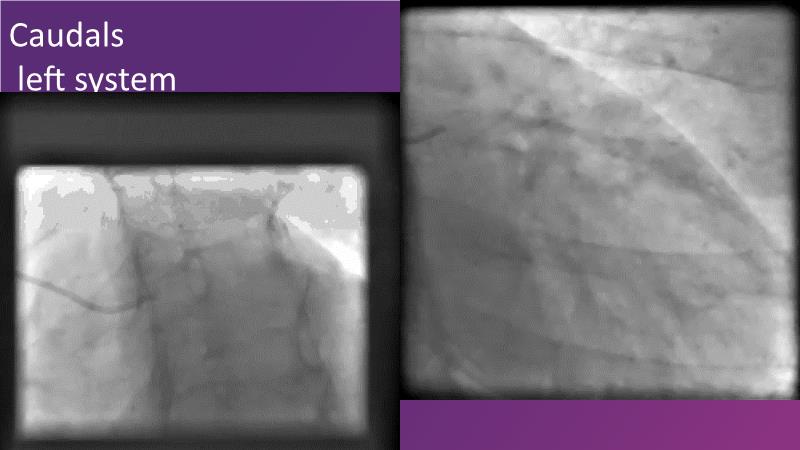

DES and DCB, can these two technologies be complementary for the treatment of the same patient? What are the advantages and how to proceed? You will know everything by watching this presentation based on concrete cases.

- To appreciate short and long-term angiographic results